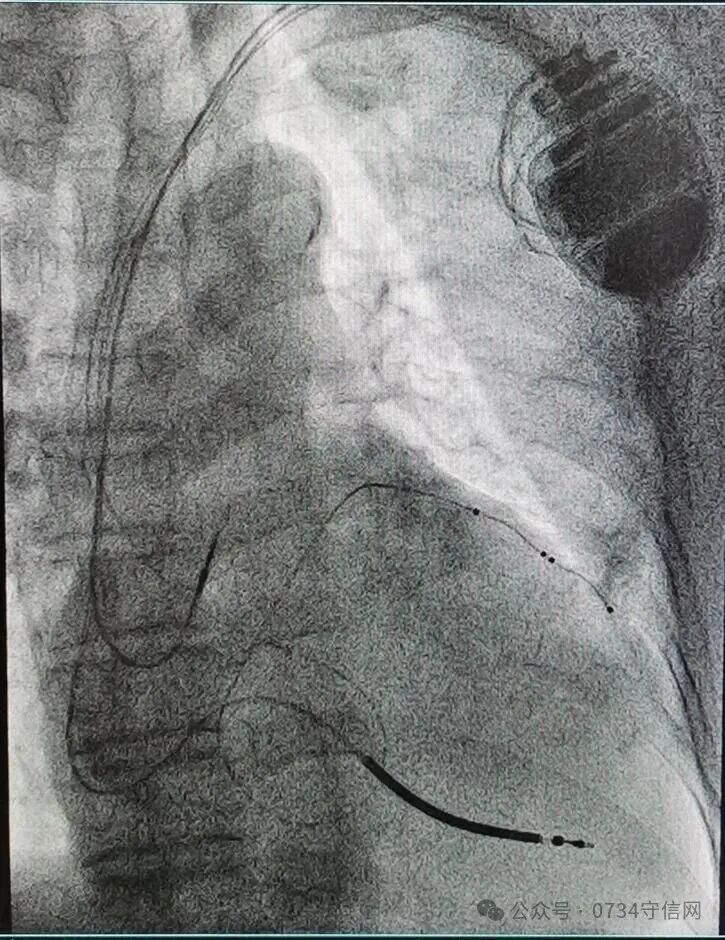

——衡阳市第一人民医院成功开展衡阳地区首例3.0T MRI兼容CRTD植入术

近日,衡阳市第一人民医院心血管内科专家团队成功为一名终末期心力衰竭患者,实施了衡阳地区首例3.0T磁共振(MRI)兼容心脏再同步化治疗心律转复除颤器(CRT-D)植入术。此项技术的开展,填补了区域内该领域的技术空白,标志着该院心脏起搏与电生理诊疗技术实现了跨越式提升,为当地心衰患者带来了新的生命守护方案。

作为心力衰竭治疗的“终极武器”之一,CRT-D(俗称“三腔除颤器”)是集治疗与防护于一体的高端医疗设备。它既具备心脏再同步治疗(CRT)的核心作用,又拥有植入式心律转复除颤器(ICD)的急救功能,为患者的生命安全拴上“双保险”。此次手术的关键突破在于“3.0T MRI兼容”。传统CRTD设备因受电磁兼容性限制,患者术后无法接受高磁场强MRI检查,而MRI作为多种疾病(如肿瘤、脑血管疾病)的重要诊查手段,其检查限制往往给患者后续诊疗带来极大困扰。3.0T MRI兼容型CRTD的成功应用,彻底打破了这一壁垒,患者术后可自由接受3.0T MRI检查,既不影响设备正常工作,又能获得全面精准的后续诊断,极大提升了治疗的安全性与便利性。